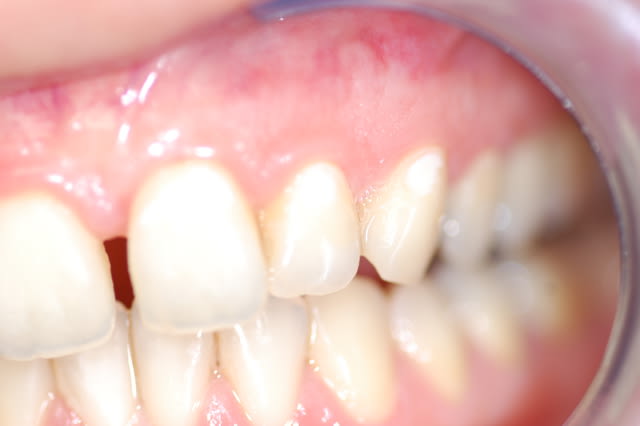

mon interrogation du jour, cette patiente de 40 ans qui vient d'accoucher me signale les "taches blanches et sensibles apparues il y a peu..." je confirme qu'il y a des déminéralisations sur 21 22 et 23 qui n'existaient pas il y a un an; je l'ai questionné sur le régime alimentaire en insistant bien: ras.

La photo jointe est pourrie je les ai ttes foirées et c'est la moins pire :(